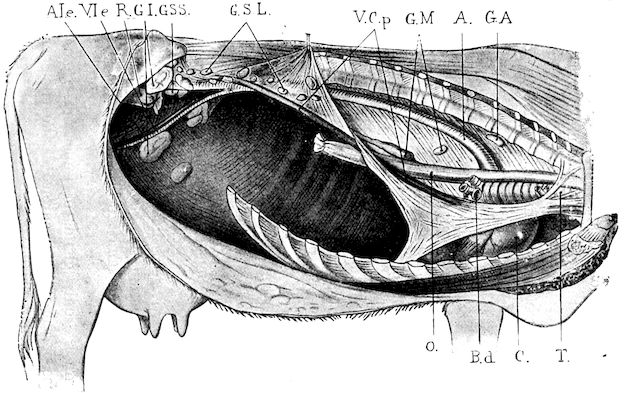

| Rumen | 737 | |||

| Puncture of the rumen | 737 | |||

| Gastrotomy | 739 | |||

| Laparotomy | 740 | |||